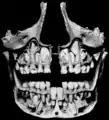

Diente permanente sin erupcionar bajo la línea de la dentición decidua.